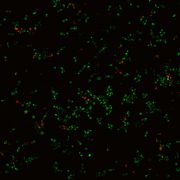

Confocal laser scanning microscopy shows that C. albicans develops biofilms on a plastic surface (left photo), and addition of purpurin suppresses biofilm formation (right photo). Green cells are living and red cells are dead.